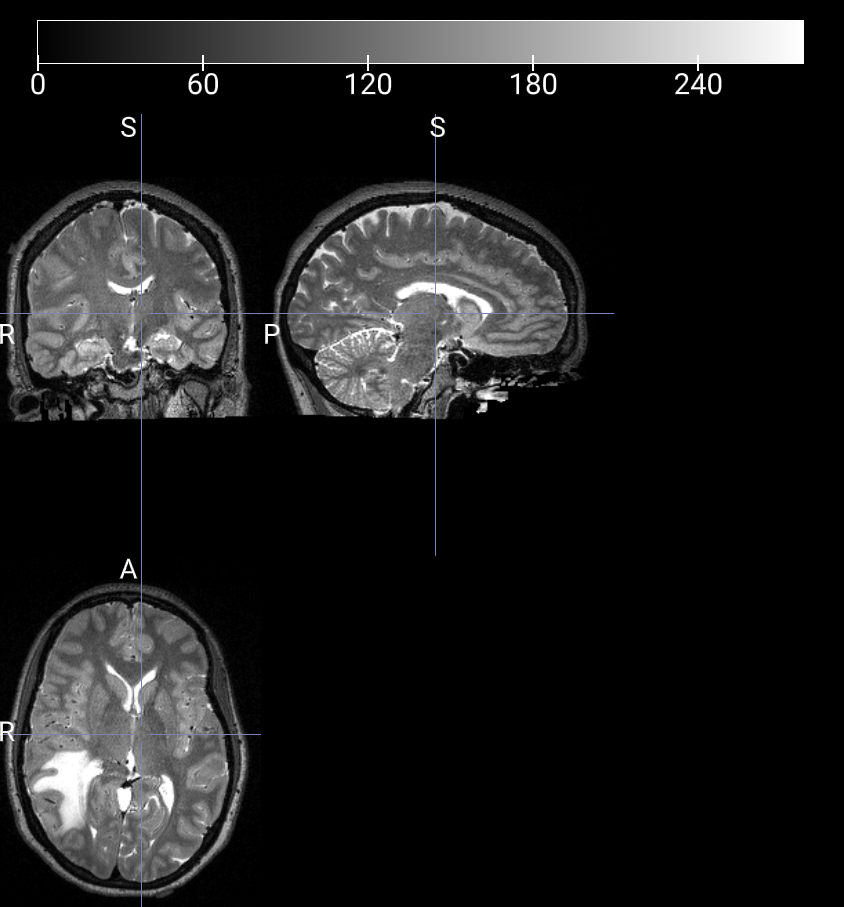

数据样本可视化

T1W 3D 图像

T2W 3D 图像